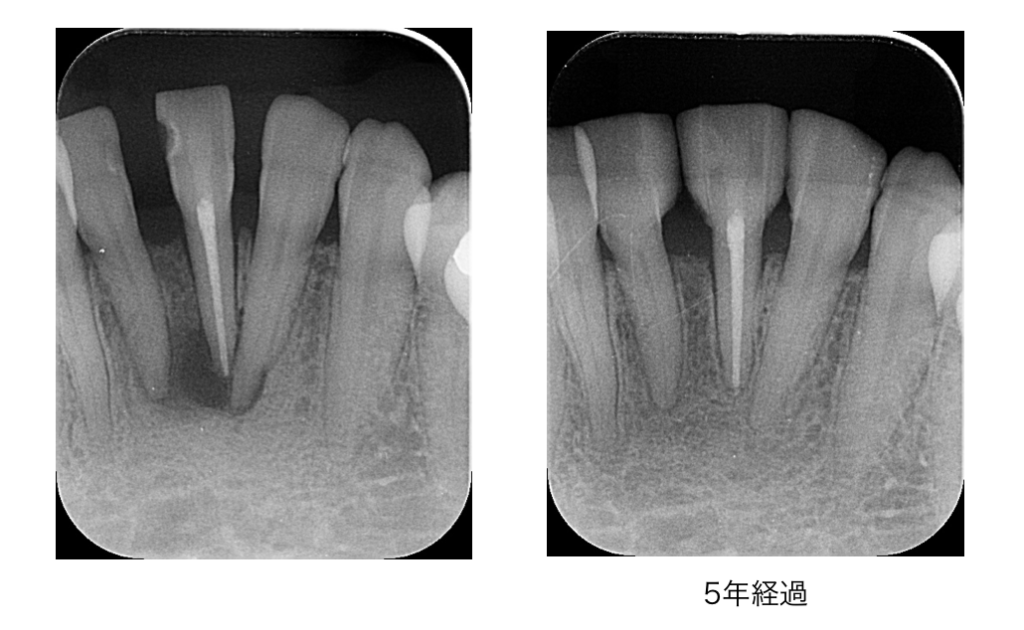

MTAセメントとは?|生体にやさしく神経を守る歯科材料

MTA(Mineral Trioxide Aggregate)セメントは、歯科医療で使用される生体親和性の高い薬剤です。

● MTAの主な特徴

細菌…